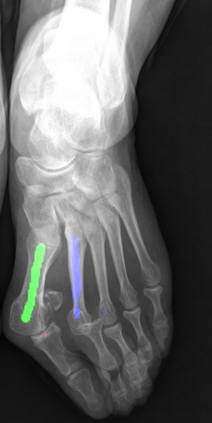

Angular measurements is essential to make a resonable treatment for Hallux valgus (HV), a common forefoot deformity. However, it still depends on manual labeling and measurement, which is time-consuming and sometimes unreliable. Automating this process is a thing of concern. However, it lack of dataset and the keypoints based method which made a great success in pose estimation is not suitable for this field.To solve the problems, we made a dataset and developed an algorithm based on deep learning and linear regression. It shows great fitting ability to the ground truth.